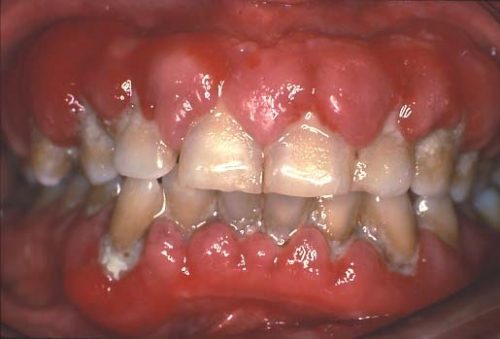

باد کردن لثه دندان به دلیل مصرف دارو

مصرف برخی از داروها می تواند علت متورم شدن لثه شود. بر خلاف مورد قبل، در این حالت بافت های لثه معمولا سفت و صورتی رنگ بوده و به لمس حساس نیستند و به راحتی خونریزی نمیکنند. گاهی علت علت ورم لثه پشت دندان همین مورد است.

در موارد شدید ممکن است تاج دندان به طور کامل لثه را پوشانده و موجب بیماری لثه شود چرا که در این شرایط تمیز نگه داشتن دندانها دشوار میشود. همچنین مشکلات مربوط به بیرون زدن دندان و همراستایی آنها نیز ممکن است اتفاق بیفتد. تورم لثه به واسطه مصرف دارو پس از قطع مصرف، ممکن است به طور کامل یا تا حدی برطرف شود. در صورتی که نمیتوانید مصرف دارو را متوقف کنید باید با جراحی بافت اضافی لثه برداشته شود. به این عمل جراحی ژنژیوکتومی گفته میشود. با این حال باز ممکن است در صورت ادامه مصرف دارو لثه بزرگ شود. از آنجایی که این وضعیت با تجمع پلاک در دندانها بدتر میشود، رعایت بهداشت مناسب از شدت آن میکاهد. به نقل از clevelandclinic: